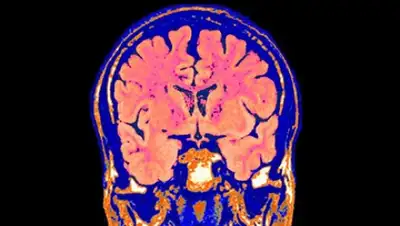

Американская биотехнологическая компания Bioquark планирует доказать, что смерть мозга не является необратимой, и разработать технологии «оживления» главного органа человеческого организма.

Пастор и ее коллеги запустили проект ReAnima — чтобы исследовать потенциал последних биомедицинских технологий для «реанимации» головного мозга. Ученые начнут клинические испытания с участием людей, которых в США и Великобритании официально признали мертвыми, но продолжают поддерживать в вегетативном состоянии («живые трупы»).

Уже получено разрешение на первый этап клинических испытаний. Исследователи будут работать с группой пациентов 15-65 лет, попавших в состояние мозговой смерти из-за черепно-мозговой травмы. С помощью пептидов, стволовых клеток, лазеров и стимуляции нервов ученые постараются добиться оживления тканей мозга.

Первые результаты ожидаются уже через два-три месяца. Исследователи надеются пронаблюдать (на томографе) симптомы оживления на границе верхнего отдела спинного мозга и нижней зоны мозгового ствола (этот участок, в частности, отвечает за дыхание и сердцебиение).

Изображение: SCI / Globallookpress.com